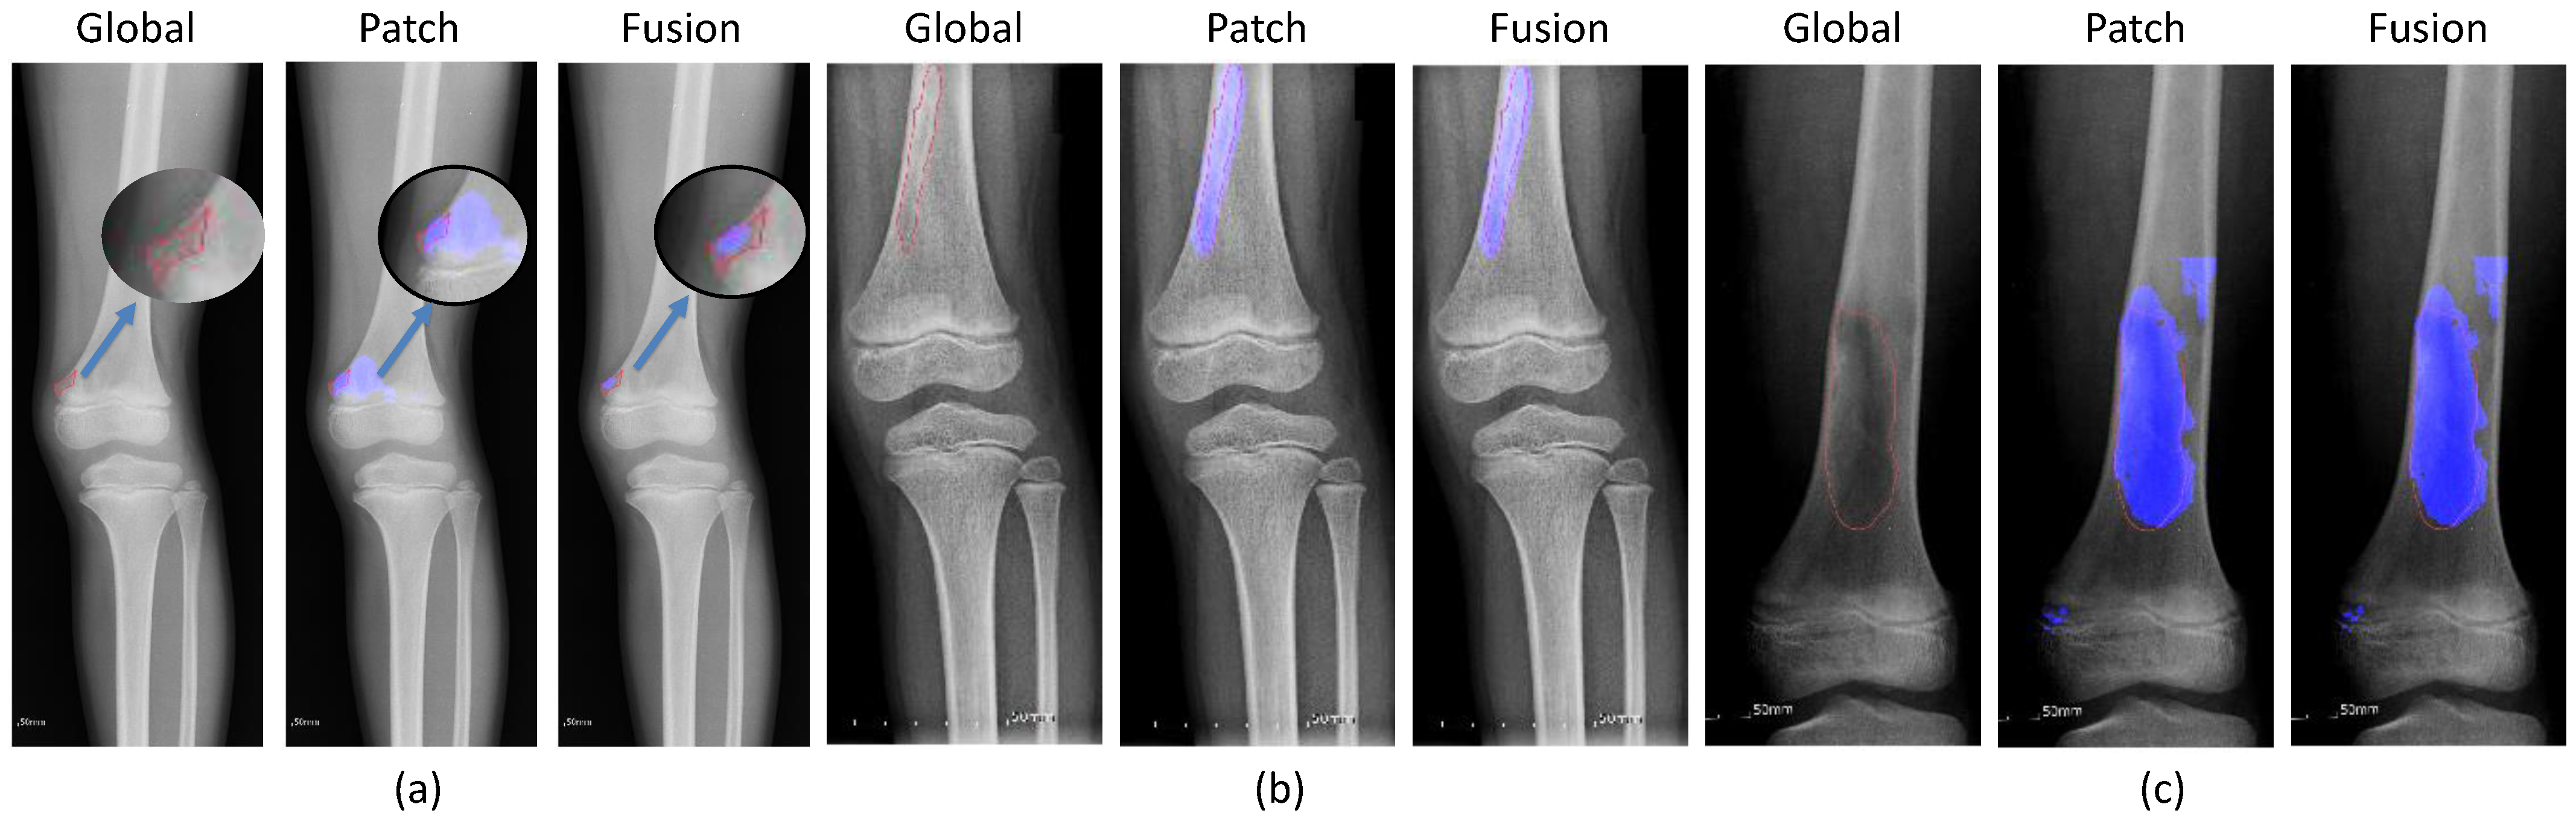

2.2.2. Global and Patch-Based Models

3.1. Experiments on Tumor Segmentation